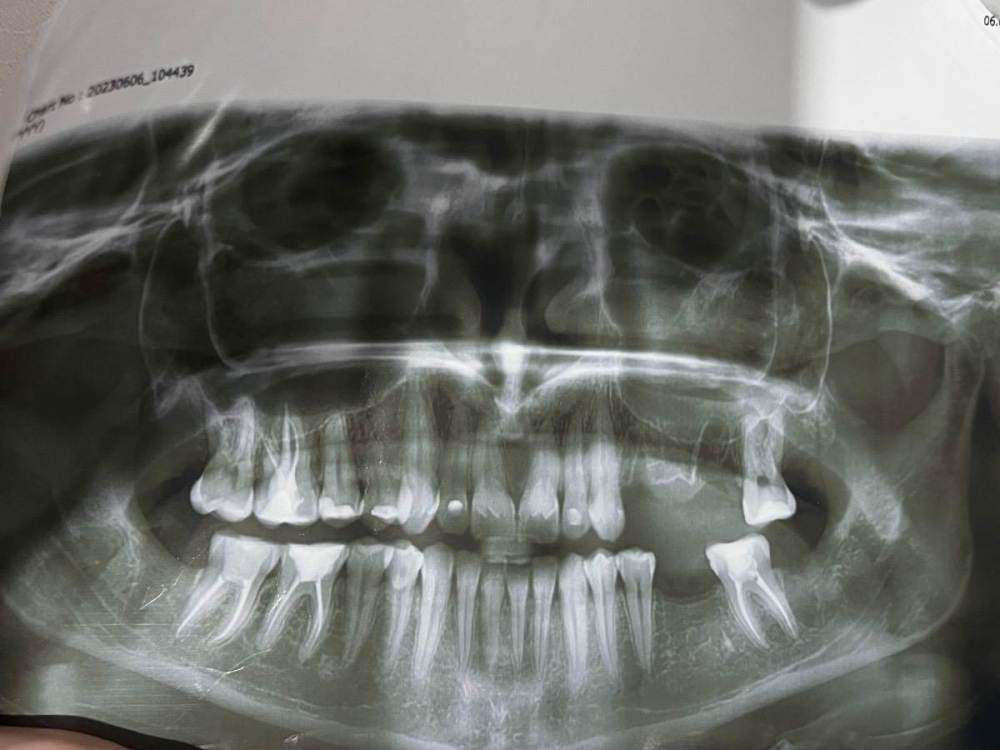

Alisapanadol Опубликовано 10 июня, 2023 Поделиться Опубликовано 10 июня, 2023 Ребята всем привет, ситуация такая , удалили восьмёрку снизу долбили молоточком и тд , после зашили поставили бандаж. Бандаж сняли через сутки и сняли швы на следующий день так как лунка ударяла током прям подергивала после снятия швов сделали кюртаж, через пару дней подергивание током прошло и началась ноющая боль , не понятно откуда то от от лунки то ли от 7зуба, кюртаж лунки 8 делали один раз, все без изменений , антибиотики пила 8 дней так как удаляли ещё три зуба сверху. Ходила к трём разным врачам спрашивала за соседний 7 зуб, говорят все нормально пролечен боль давать не может. Такое чувство , что обезболивающие эту ноющую боль не снимают, ходила на физио два раза без результата, сама лунку промываю под напорном шприца внутрь лунки полоскаю и тд, 12 день после удаления. Прилагаю снимок до и после . Спасибо за помощь дай вам бог здоровья Вопрос: воспаление троичного нерва или соседний зуб гадит? Ссылка на комментарий